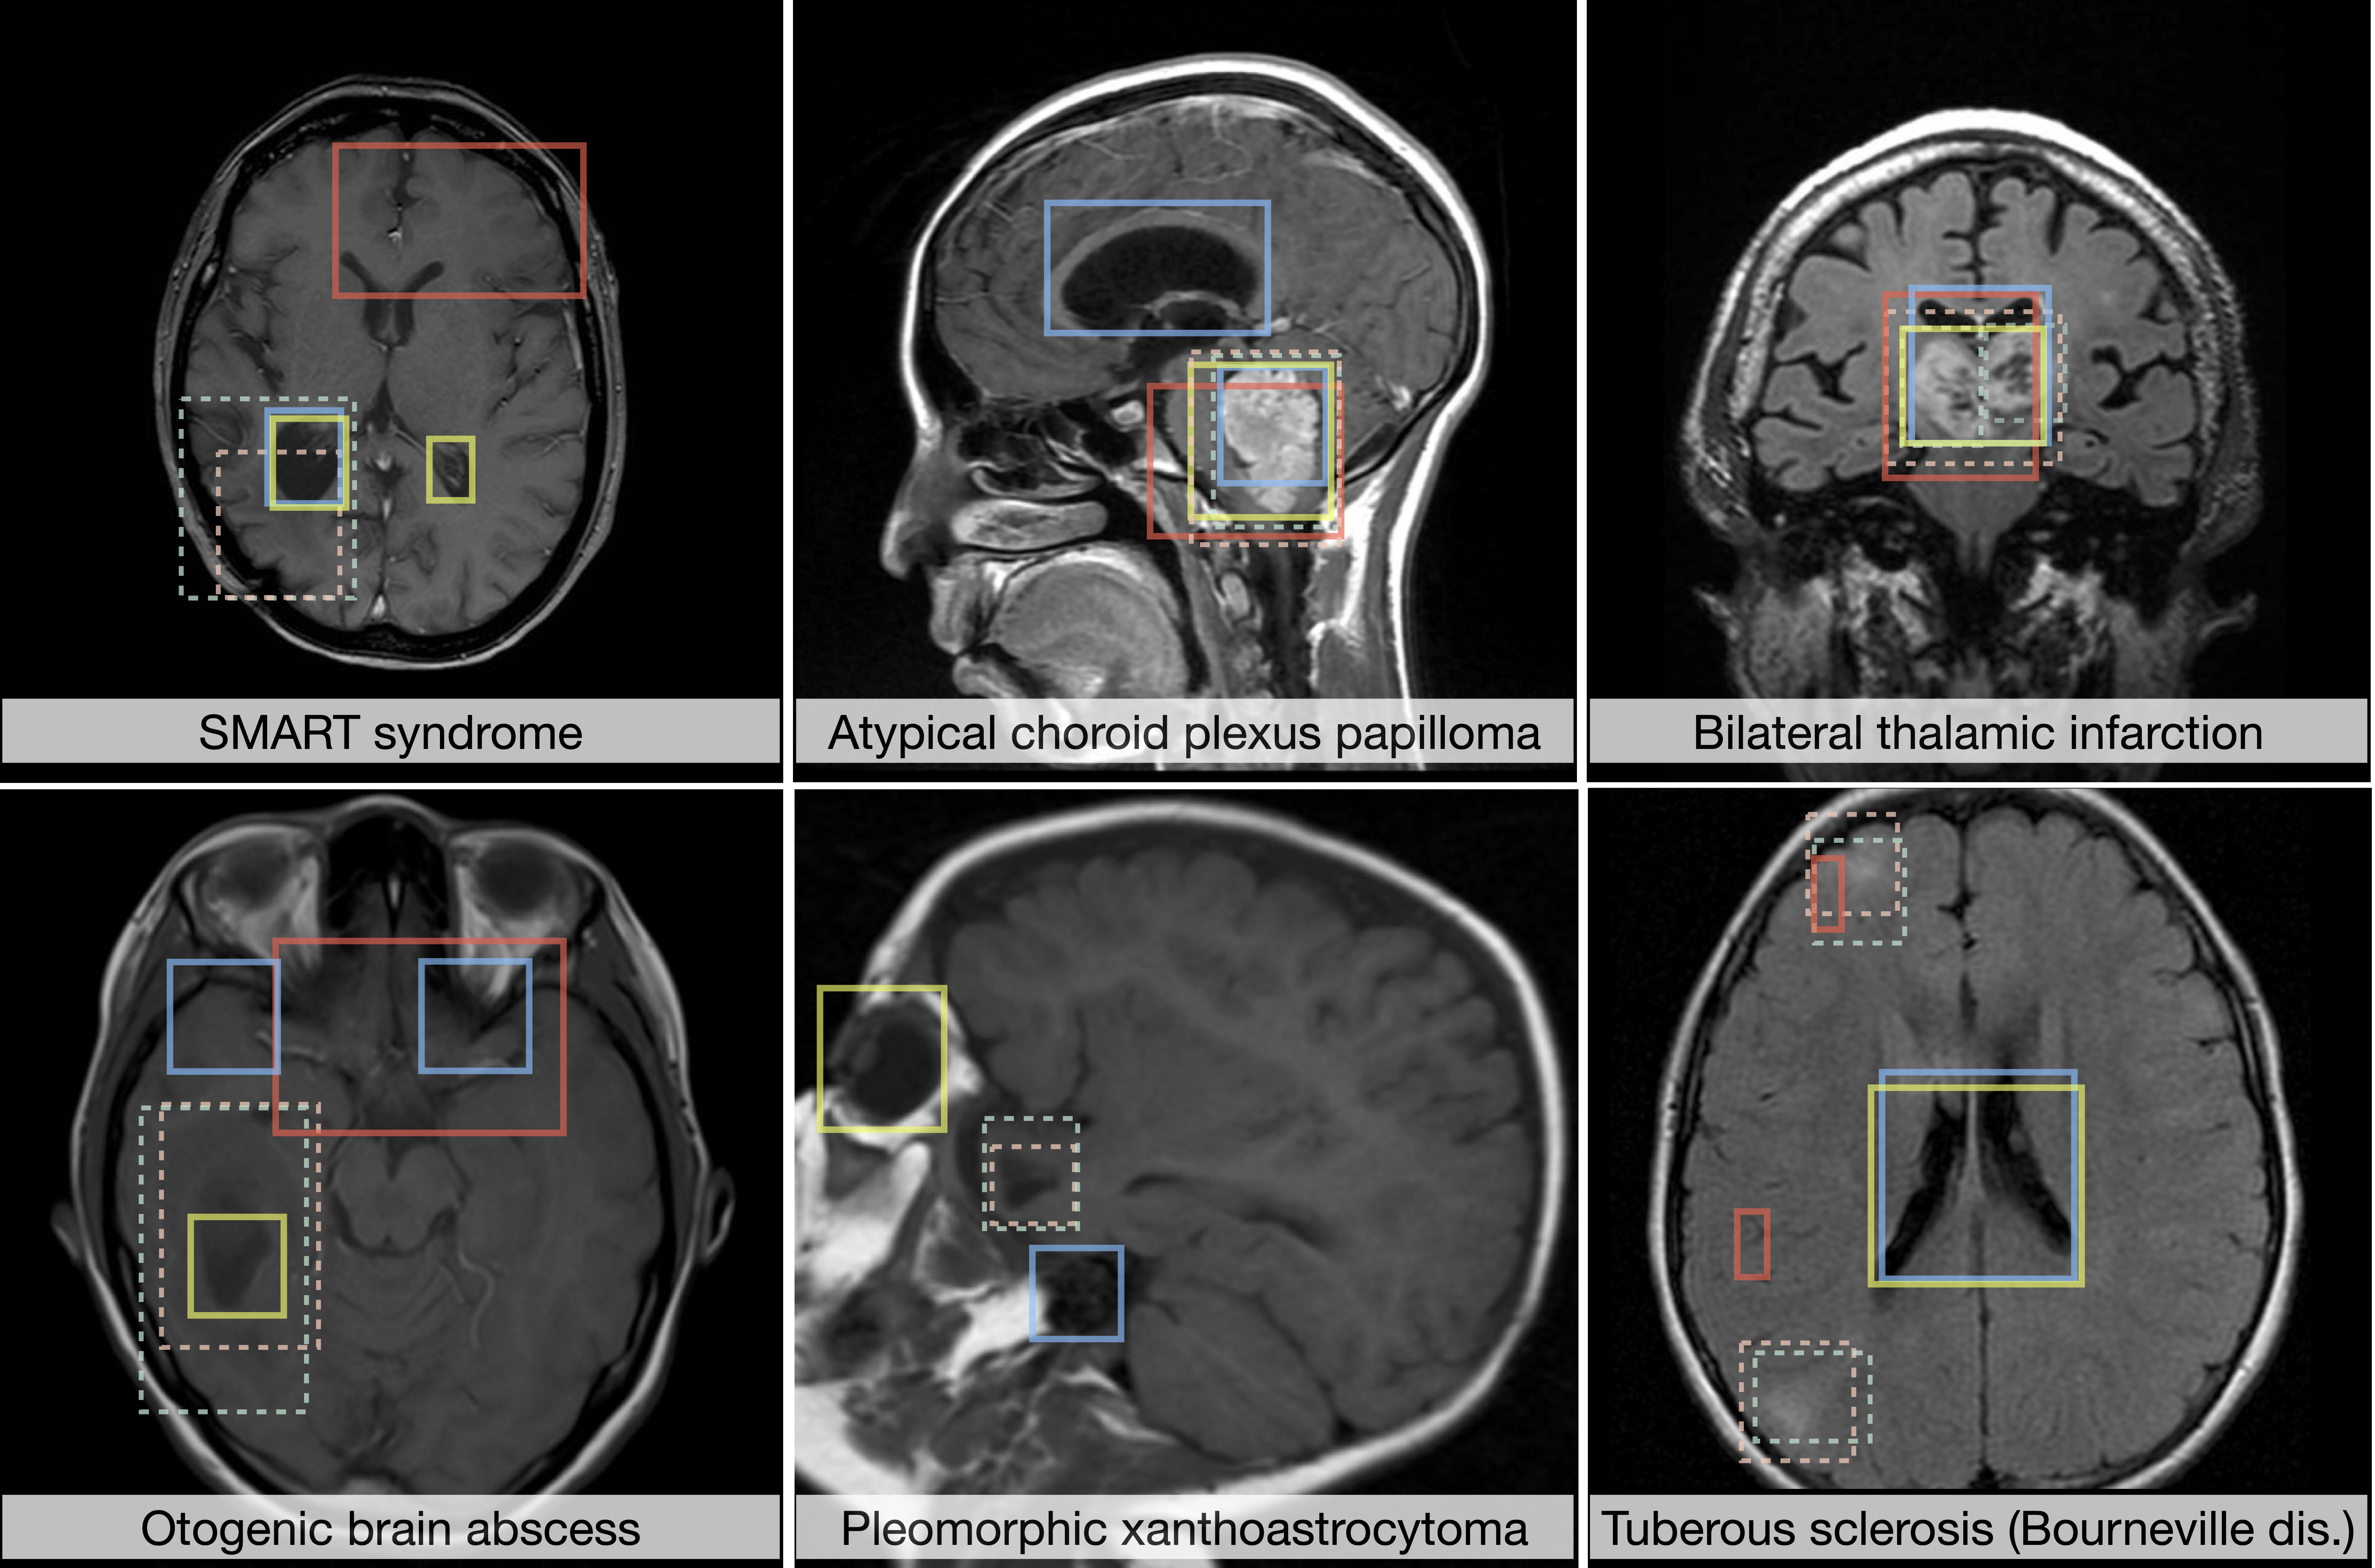

Identifying rare clinical phenotypes and resections without expert labels through OOD detection.

"Unsupervised Anomaly Detection (UAD) is formulated as a label-free approach for open-world clinical settings, where the space of possible pathologies is inherently unbounded, yet is predominantly developed and evaluated under closed-world assumptions tied to known anomaly distributions. We reframe UAD as a problem of generalizing anomaly discovery by grounding detection in principled modeling of the normative anatomical manifold, enabling reliable identification of rare, heterogeneous, and previously unseen disease phenotypes."

Integrity of Open-World Generalization

Establish datasets and evaluation protocols that explicitly stress test UAD methods under open-world conditions, including rarity, heterogeneity, and previously unseen disease phenotypes.